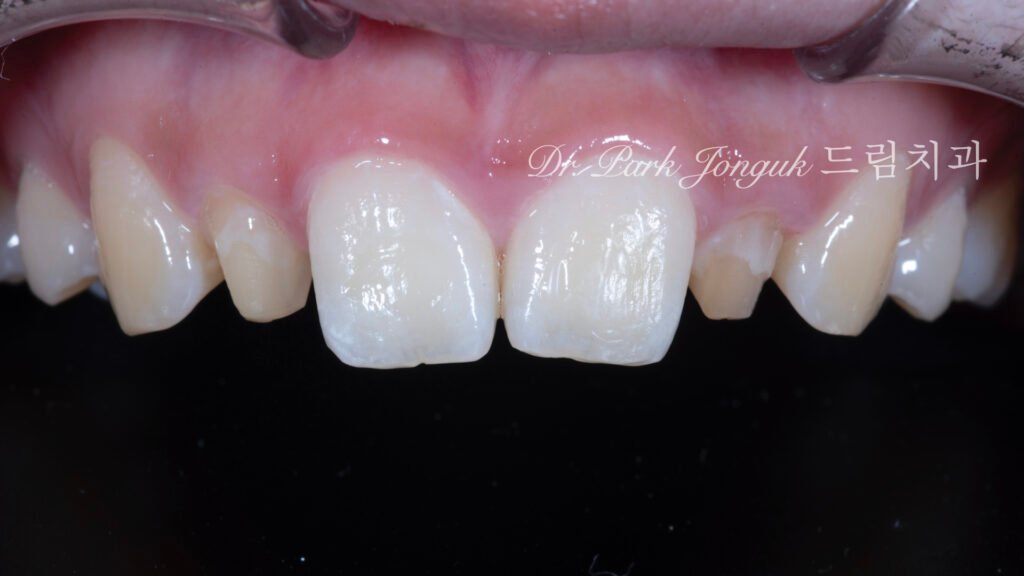

내원 환자는 과거 타 의료기관에서 왜소측절치에 대한 라미네이트 치료를 받은 이력이 있었으나, 조기 탈락(debonding)이 발생하여 재치료를 원했습니다. 초진 검사 결과 재치료를 복잡하게 만드는 여러 요인이 확인되었습니다.

1. 부적절한 기존 치아 준비 왜소측절치는 본질적으로 작은 치아이므로 치아 삭제가 불필요하거나 최소한이어야 합니다. 그러나 이 환자의 경우 이전 치료 시 과도한 치아 삭제가 시행된 상태였습니다. 이는 재치료 시 라미네이트 두께가 증가해야 함을 의미하며, 심미성과 접착 강도 측면에서 불리한 조건을 만듭니다.

2. 현저한 중절치 비대 왜소측절치와 대조적으로 중절치는 정상 범위를 상당히 초과하는 크기였습니다. 중절치:측절치 비율이 극심하게 불균형한 상태로, 단순히 측절치만 확대하면 오히려 부조화가 심화될 수 있는 케이스였습니다.

3. 비후된 치근 형태(Thick Root Morphology) 이 케이스의 가장 큰 도전 과제는 중절치의 치근이 상당히 굵다는 점이었습니다. 비후된 치근은 여러 임상적 어려움을 만듭니다: